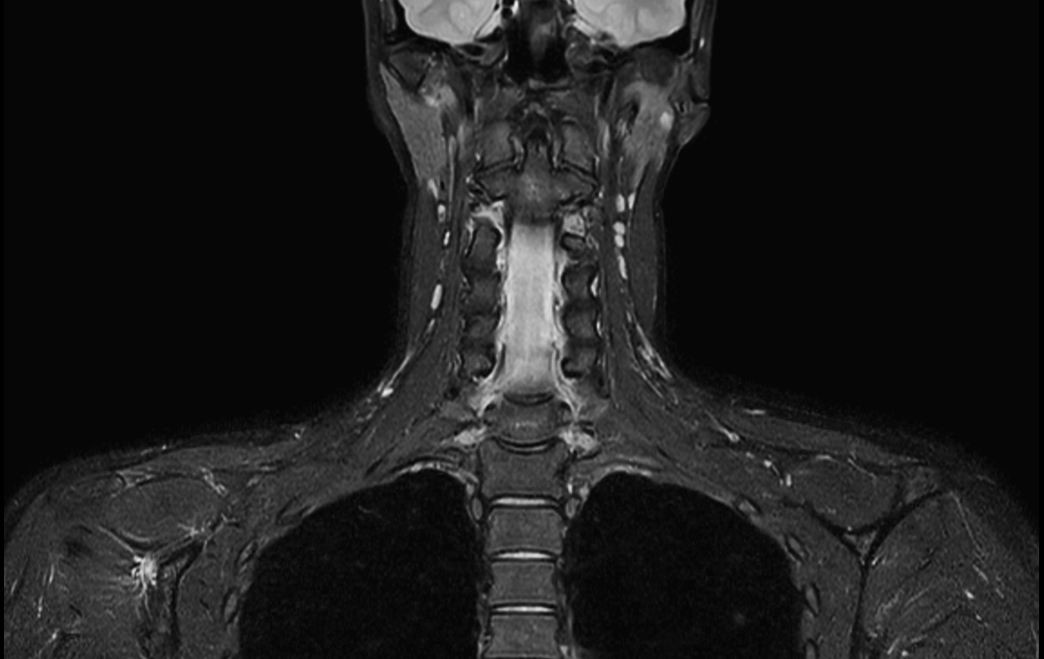

Coronal T2w  mDIXON TSE (Water)